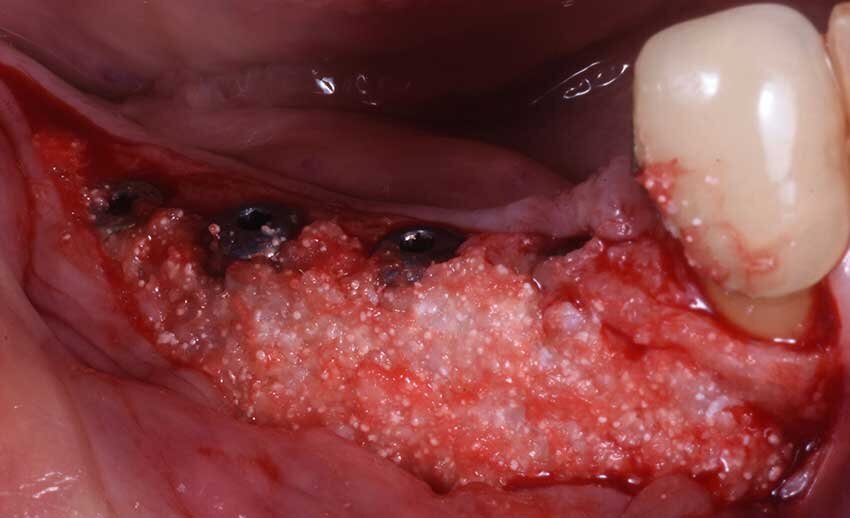

La rx post-operatoria evidenzia bene come nel sito 46 l’impianto fosse ancorato all’osso solamente dalla sua porzione apicale, mentre l’immagine clinica (Fig. 5) mostra quanto ognuno dei quattro impianti (Neodent-Straumann) presentasse una evidente deiescenza vestibolare con almeno 5-6 spire esposte fuori cresta e una evidente insufficienza di volume in senso orizzontale (Fig. 6). Per questa specifica situazione clinica si selezionò un materiale (GTO Osteobiol) da innesto con caratteristiche particolari, appiccicoso e capace di creare e mantenere il volume anche in una situazione anatomicamente sfavorevole. Questo bio-materiale è composto da osso suino collagenato associato a un gel termo sensibile (TSV gel) che gli consente di “gellificare” e diventare solido al contatto con l’umidità della bocca. Queste caratteristiche lo rendono facilmente plasmabile al difetto e nello stesso tempo stabile, dalla figura 6 si può notare come questa stabilità consenta di apporre una quantità di materiale adeguato a correggere il difetto della cresta e a proteggere le spire degli impianti altresì esposte (Fig. 7).